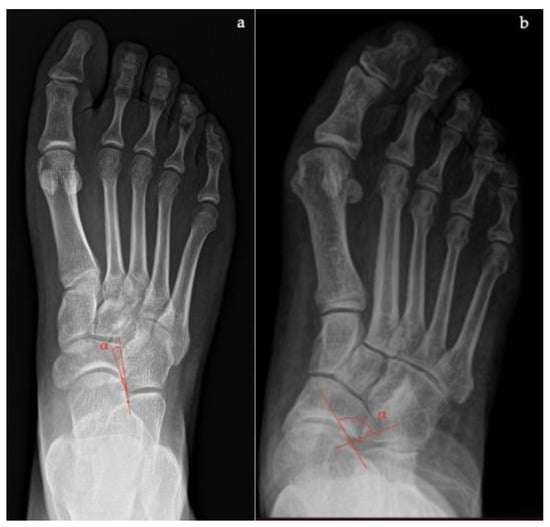

- Talar–first metatarsal angle, between the lines drawn along the long axis of the talus and the first metatarsal (normal 0°, flatfoot: mild >4°, moderate >15°, severe >30°) (Figure 1);

- Talonavicular coverage angle, between the line that joins the medial and lateral articular margins of the talus, and the line that joins the medial and lateral articular margins of the navicular, it represents forefoot abduction (normal, <7°; flatfoot, >7°) (Figure 2);

- Talonavicular uncoverage percentage, the percentage of the talus that is not in contact with the navicular medially, useful to evaluate forefoot abduction (normal, 10% to 30%; flatfoot >30%) (Figure 3);

- Talar incongruency angle (normal, 5° = –26°; flatfoot >26°), is formed by the intersection between a line from the most lateral point of the articular surfaces of the talus and the navicular, and a line from the lateral aspect of the talar neck (in its most narrow segment) to the lateral point of the talar articular surface (Figure 4).